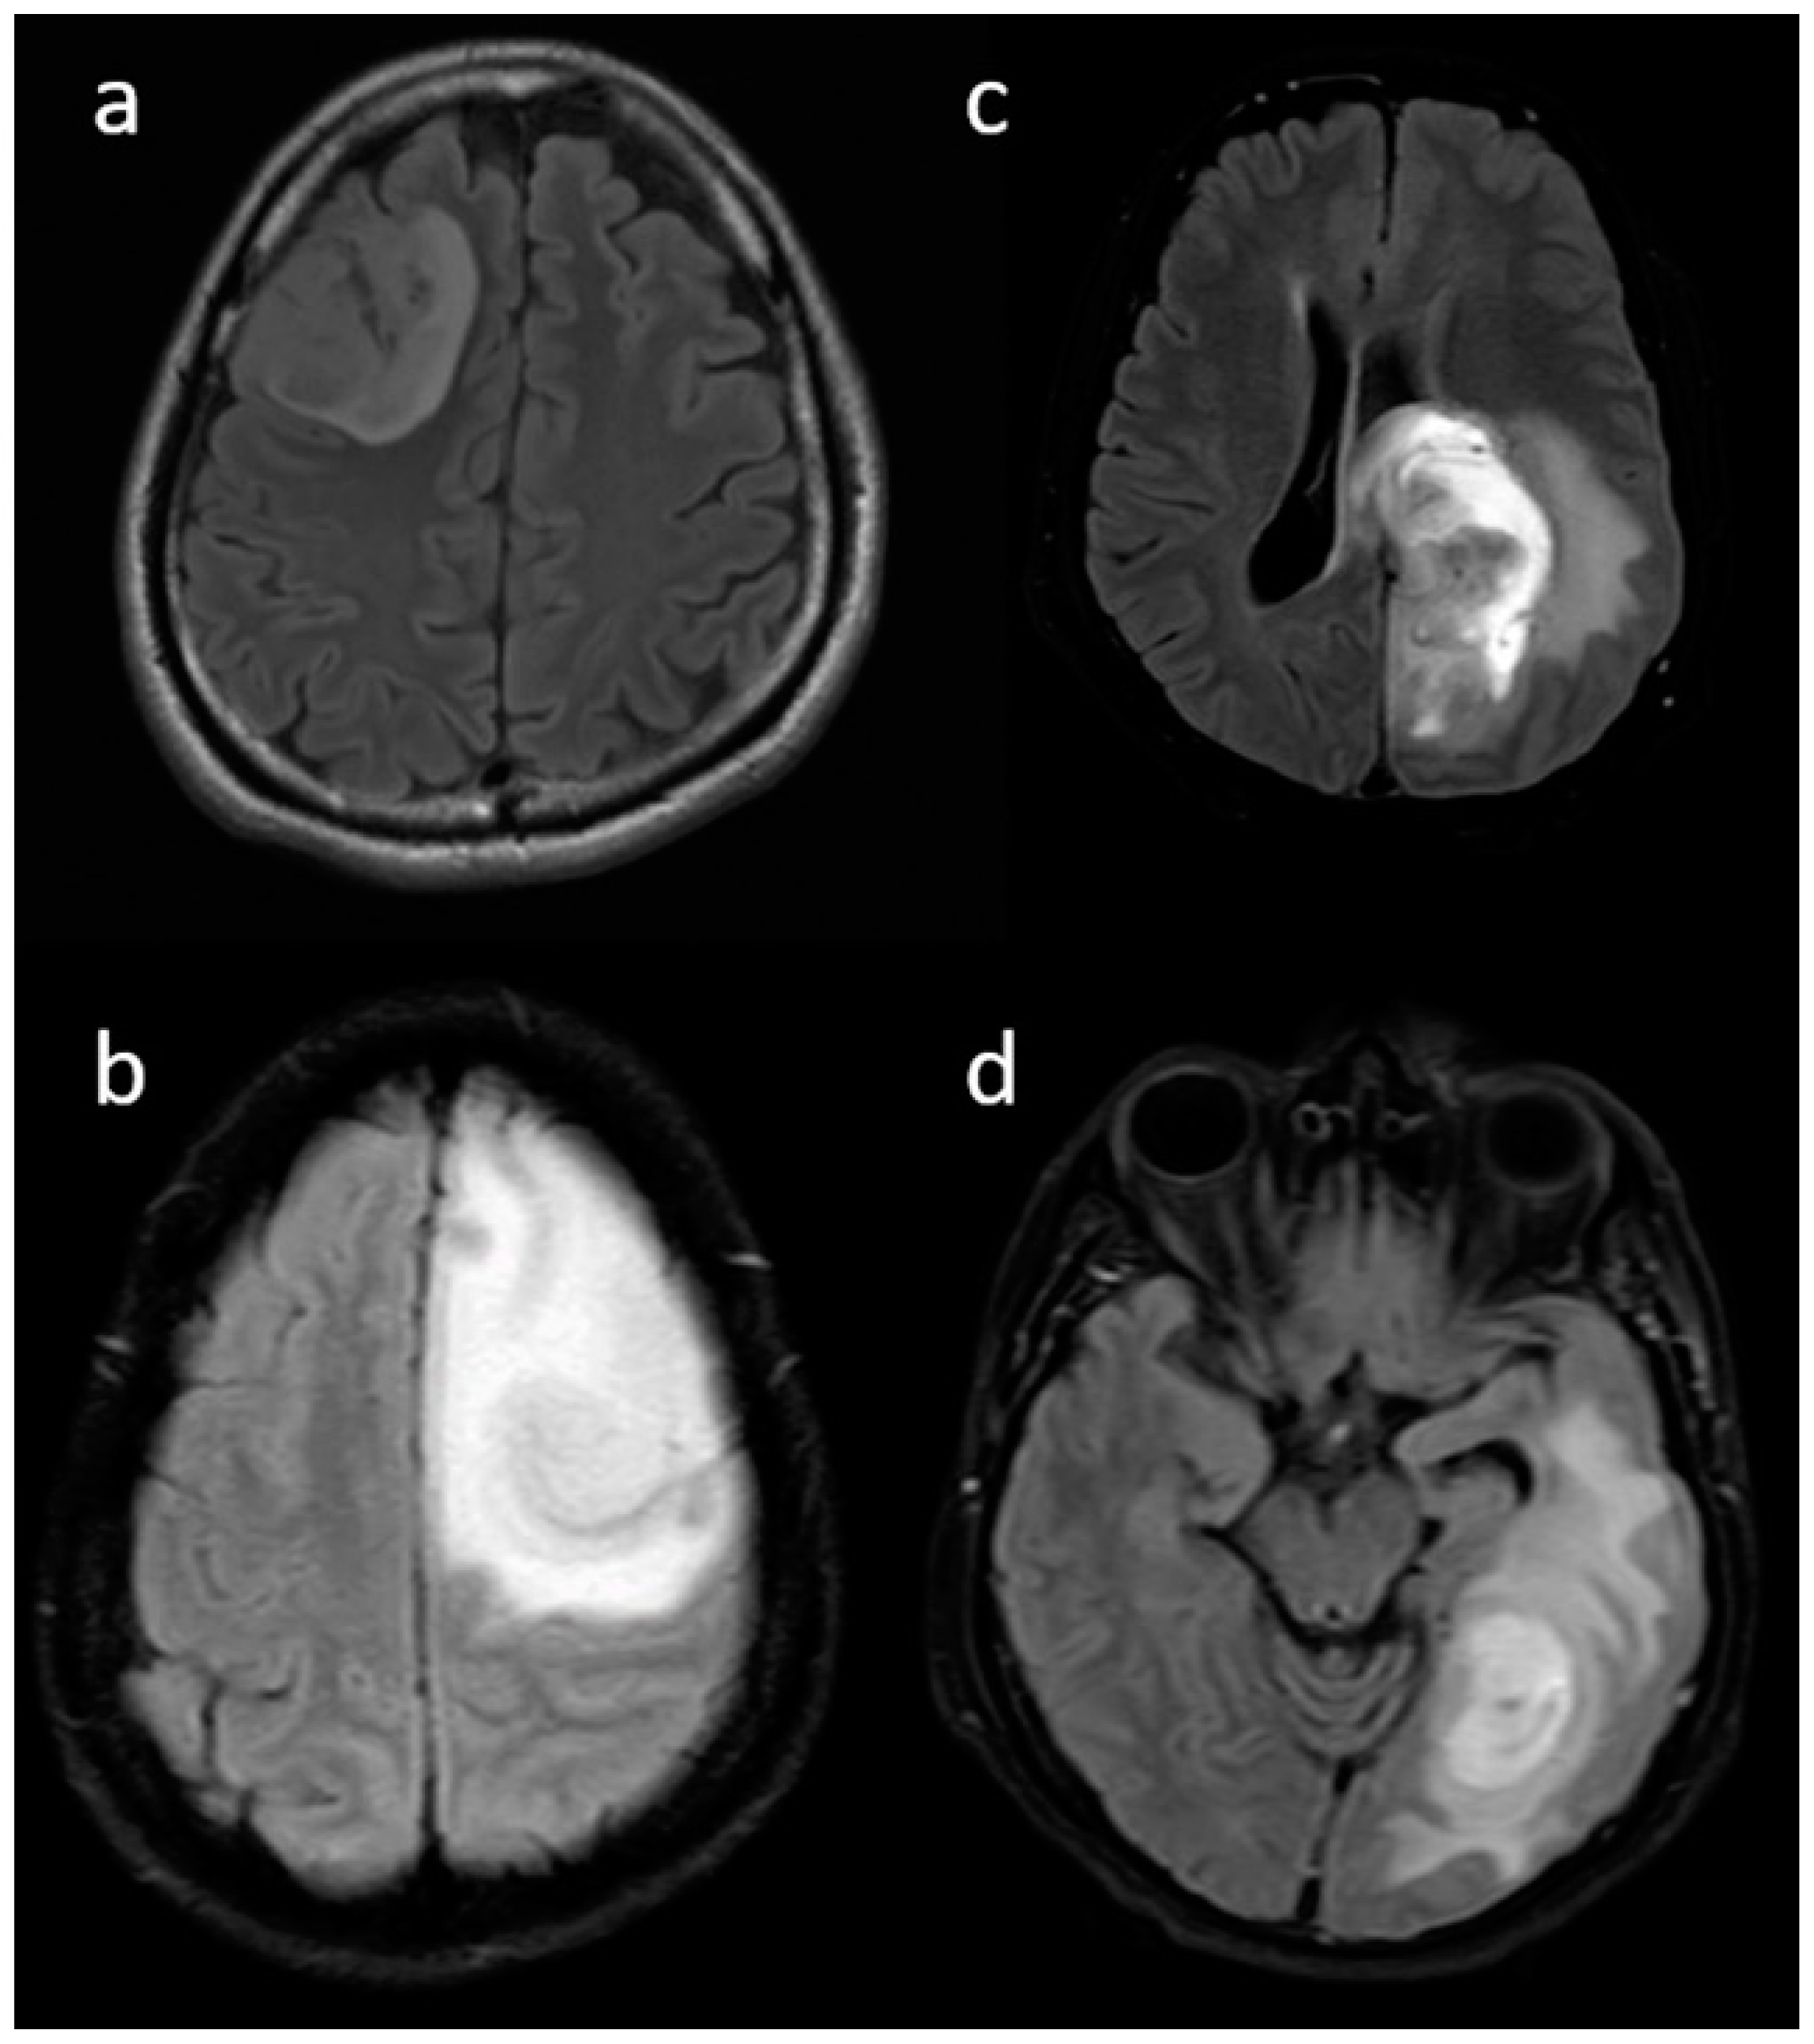

| Necrosis | None | 3 (15.8) | 3 (2.3) | <0.001 |

| <25% | 11 (57.9) | 14 (10.9) | ||

| 25- 50% | 2 (10.5) | 35 (27.1) | ||

| >50% | 3 (15.8) | 77 (59.7) | ||

| Edema | None | 3 (15.8) | 3 (2.3) | 0.025 |

| <tumor volume | 11 (57.9) | 68 (52.7) | ||

| Equal to tumor volume | 4 (21.1) | 35 (27.1) | ||

| >tumor volume | 1 (5.3) | 23 (17.8) | ||

| Cysts * | No | 11 (57.9) | 115 (89.1) | 0.001 |

| Yes | 6 (31.6) | 14 (10.9) | ||